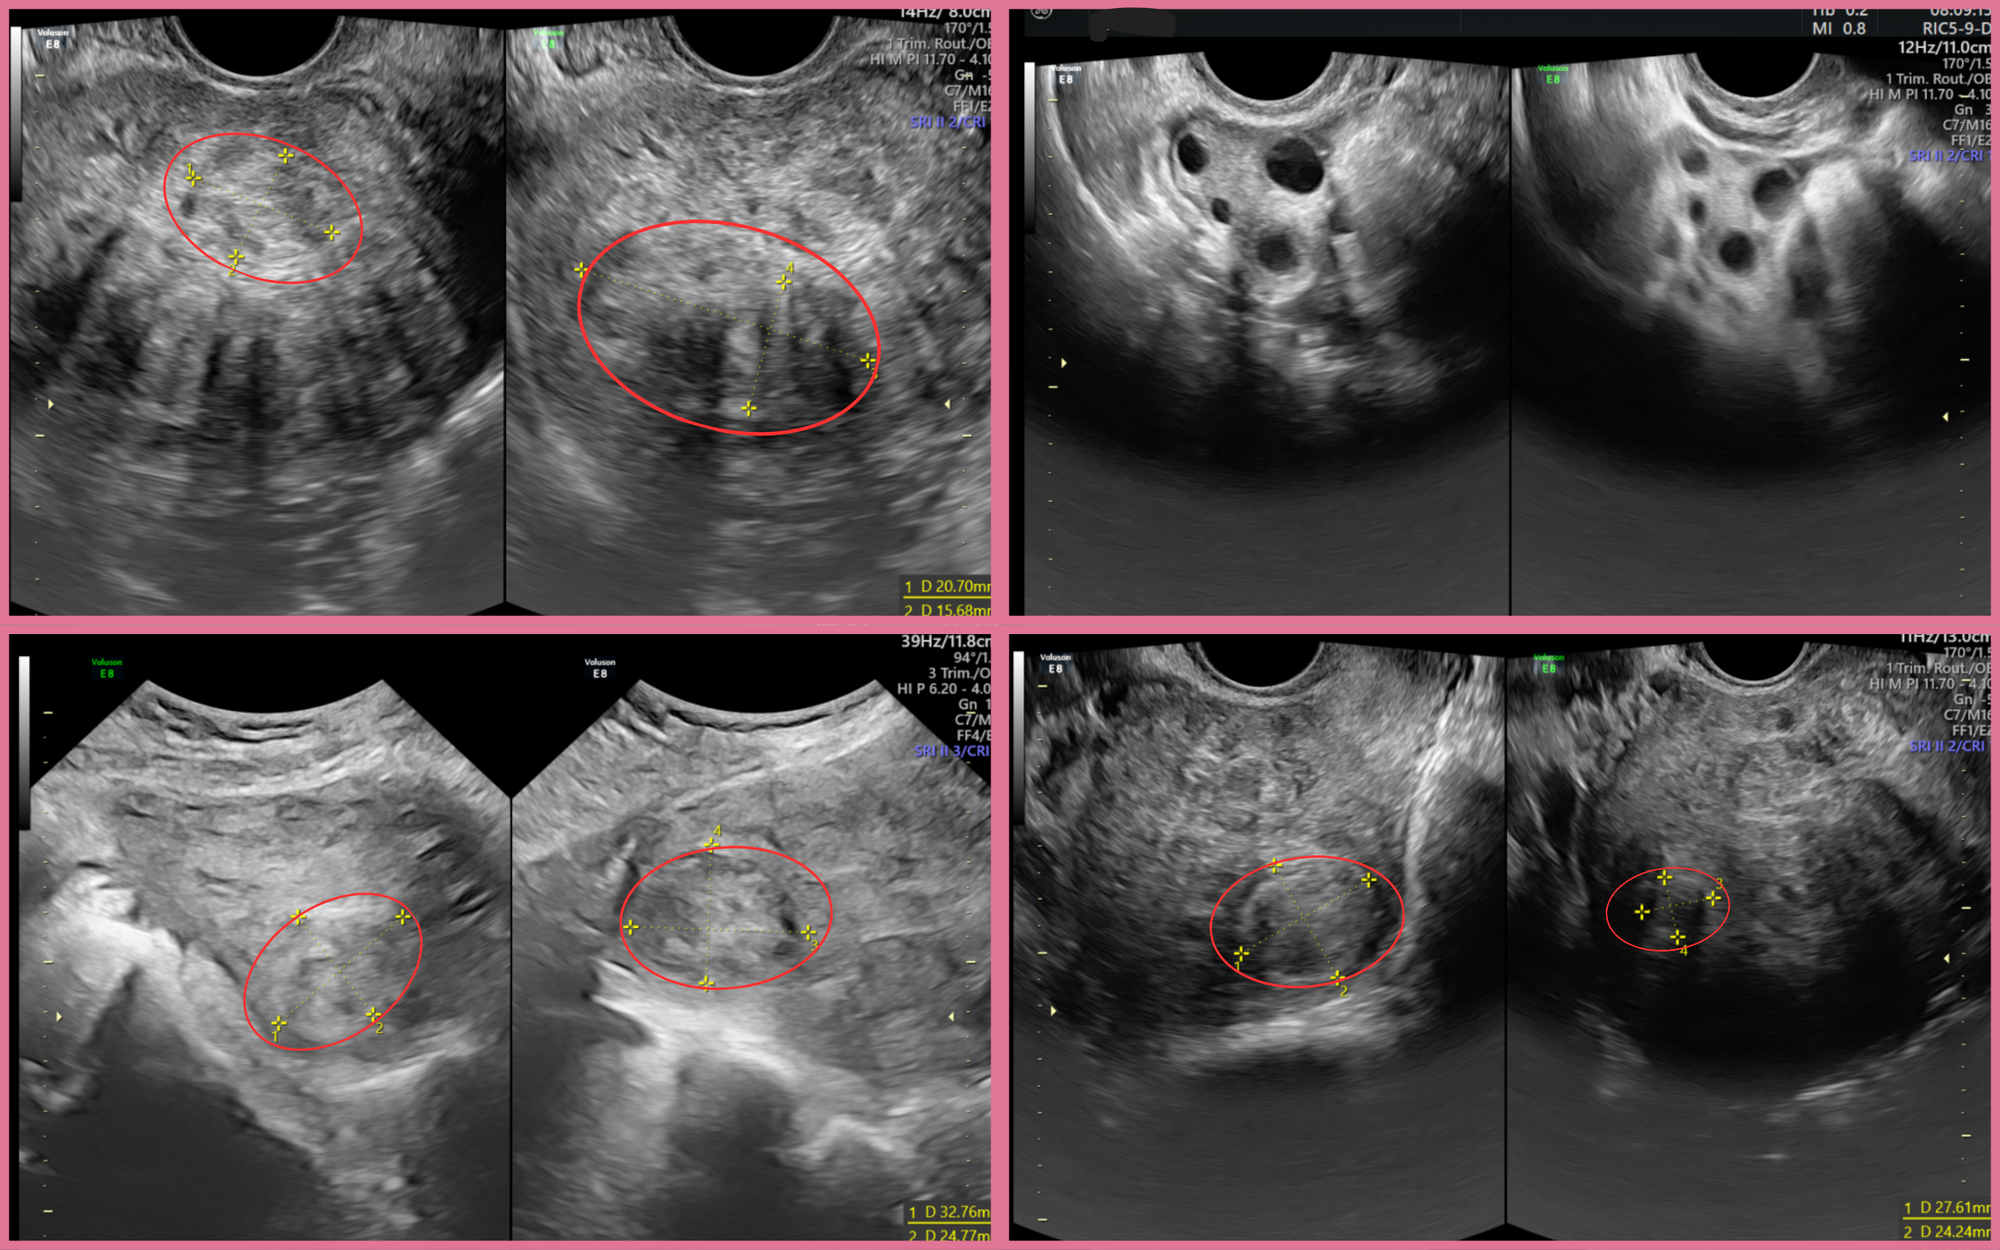

Qua thăm khám tại BVĐK Hồng Ngọc Phúc Trường Minh, các bác sĩ phát hiện tử cung của chị A có kích thước như đang mang thai 3 tháng với nhiều nhân xơ rải rác, khối lớn nhất ở thành trước kích thước hơn 4cm. Hình ảnh siêu âm cho thấy có nhiều u xơ nằm sâu trong cơ tử cung, có những khối có cuống dài và làm tử cung biến dạng hoàn toàn.

Thành tử cung biến dạng do đa u xơ.

ThS.BSCKII Nguyễn Văn Xuyên (Trưởng Đơn nguyên Phụ khoa và Tuyến vú – BVĐK Hồng Ngọc Phúc Trường Minh) cho biết: “Đa u xơ tử cung là tình trạng nhiều khối u xuất hiện đồng thời, làm biến dạng thành tử cung. Điều này khiến quá trình bong niêm mạc tử cung trong chu kỳ kinh không đồng đều, dẫn đến rong kinh kéo dài, đau bụng dữ dội. Đặc biệt trong trường hợp như chị A, số lượng lên đến 18 khối u với nhiều khối trong buồng tử cung có thể ảnh hưởng khả năng mang thai, tăng nguy cơ hiếm muộn“.

Dựa trên hình ảnh siêu âm và kết quả thăm khám, bác sĩ nhận định các nhân xơ của chị A bám sâu trong lớp cơ tử cung, nhiều khối nằm sát nhau hoặc đan xen ở các vị trí phức tạp. Đây là dạng u xơ đa ổ khó can thiệp bằng nội soi vì nguy cơ bỏ sót u và tổn thương thành tử cung cao. Vì vậy, ê-kíp quyết định thực hiện phẫu thuật mở để có trường quan rộng, dễ kiểm soát và lấy sạch toàn bộ u.